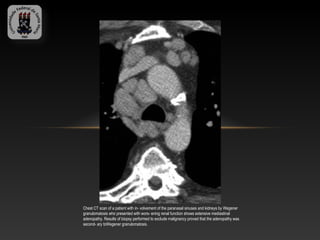

Chest CT scan of a patient with in- volvement of the paranasal sinuses and kidneys by Wegener

granulomatosis who presented with wors- ening renal function shows extensive mediastinal

adenopathy. Results of biopsy performed to exclude malignancy proved that the adenopathy was

second- ary toWegener granulomatosis.

Chest CT scanof a patient with in- volvement of the paranasal sinuses and kidneys by Wegener granulomatosis who presented with wors- ening renal function shows extensive mediastinal adenopathy. Results of biopsy performed to exclude malignancy proved that the adenopathy was second- ary toWegener granulomatosis.